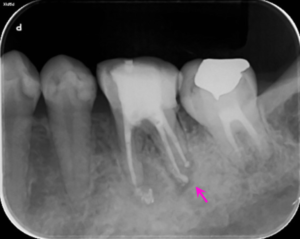

左図のレントゲン写真では根の先に炎症があり骨が溶けている部分があります(矢印部) 。

根の治療2か月後のレントゲン写真です。矢印の部分の骨の溶けている部分の大きさが小さくなっています。

根の治療4か月後のレントゲン写真です。骨の溶けている部分の透過性(黒さ)が改善して(薄くなって)、治癒に向かっている様子がうかがえます。治療後から咬む際の痛みなどの症状は無くなり、治療後2カ月で仮歯を装着されています。

根の治療9か月後のレントゲン写真です。矢印の根の先の骨の溶けている部分は無くなっています。この後、仮歯からジルコニア製のかぶせを装着されました。